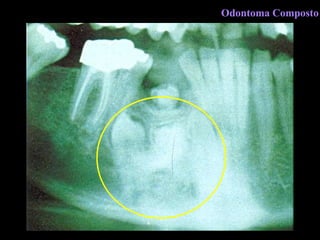

Odontoma Composto

C l í n i c a Dispostos em múltiplos dentículos irregulares Pode produzir retenção dentária Região de incisivos e caninos, de preferência Odontoma Composto

R a d i o l o g i a  Imagem patognomônica Dentículos agrupados em forma desordenada Rodeado por banda radiolúcida Limite definido, levemente corticalizado Odontoma Composto